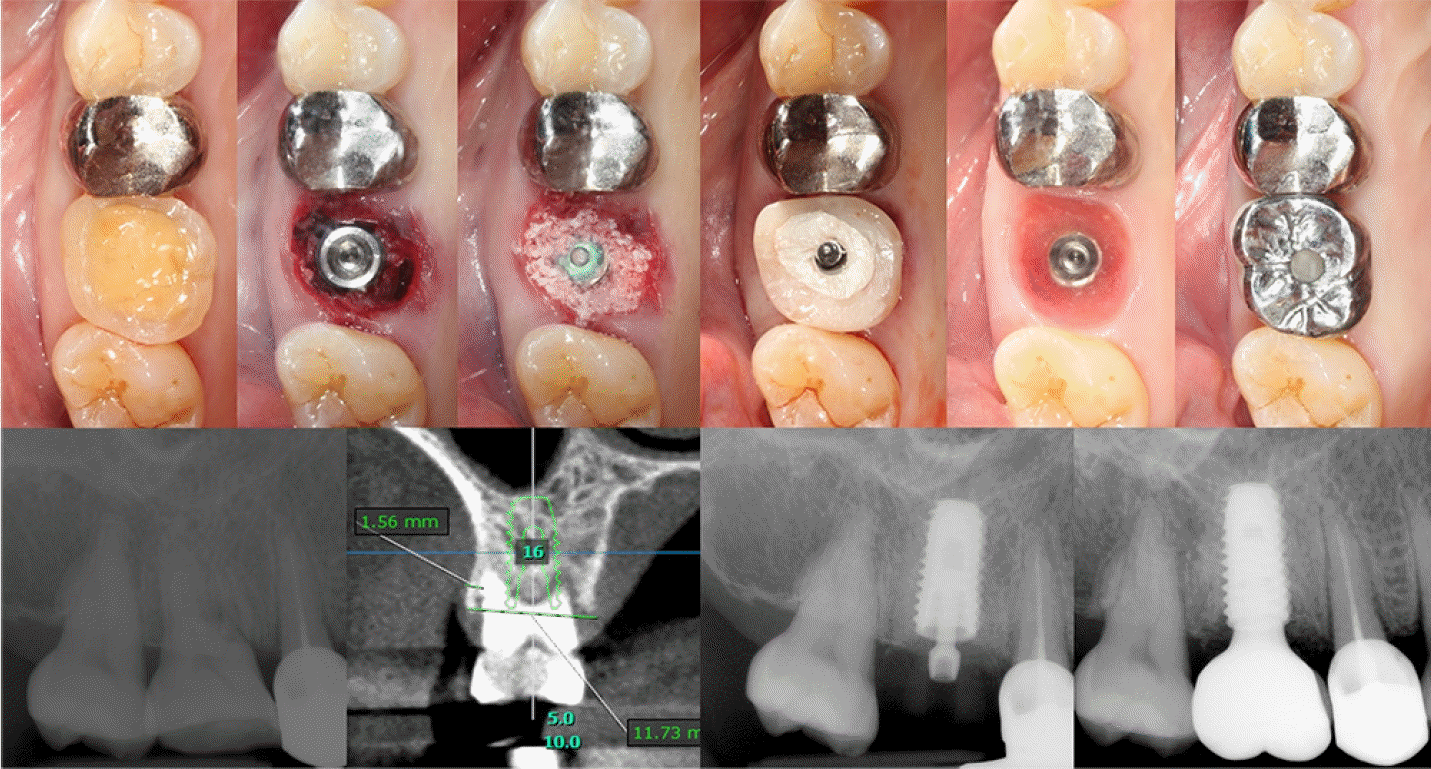

Case 3: Immediate implantation of #16i

A 73-year-old female patient was referred from the Department of Prosthodontics for extraction of the right maxillary first molar and implant placement due to a horizontal fracture of the mesiobuccal root. Preoperative CBCT showed that the buccal and palatal walls were intact, and immediate implantation was planned. After superimposing the impression obtained by an intraoral scanner(Trios 3, 3Shape, Copenhagen, Denmark) to the CBCT scan, a provisional crown was virtually designed using a computer software(Exocad, exocad GmbH, Darmstadt, Germany), matched to the crown shape of the existing tooth. The virtual provisional crown was milled from a polymethyl methacrylate(PMMA) block by a milling machine(IDC Mikro 5X, Amann Girrbach, Koblach, Austria), and then adhered to a non-hex type, pre-manufactured polyether ether ketone(PEEK) abutment(Custom Healing Abutment, Osstem, Busan, South Korea) in order to create the SSA, followed by removing the cusps to avoid any unnecessary occlusal interference with the opposing tooth(Figure 3). A 5.0 x 10mm, SLA surfaced implant(TS III, Osstem) was placed in the septal bone area after the atraumatic extraction with the deproteinized bovine bone mineral(Bio-Oss, Geistlich Parma AG, Wolhusen, Switzerland) grafted to the gap defect, and the pre-fabricated SSA was connected to the fixture to secure the surgical site without any suture(Figure 4).Case 4: Immediate implantation of #15i

Case 4: Immediate implantation of #15i

A 53-year-old female patient was referred from the Department of Conservative Dentistry for the extraction and implant placement due to the endodontic failure of the right maxillary second premolar which appeared to have an apical lesion with external root resorption. Virtual implant planning using a computer software(OnDemand3D, CyberMed Inc.) was performed with the CBCT scan. After an atraumatic extraction, active suppuration was not found therefore, an immediate implant placement was proceeded. Following thorough debridement of apical granulation tissue, an SLA-surfaced implant with the size of 4.0 x 10mm(Superline, Dentium) was placed, and porcinederived xenograft(THE Graft, Purgo Biologics) was applied to the gap defect in the buccal and palatal sides, which was secured by a collagen sponge(CollaTape, Zimmer Biomet) and HA(Healing Abutment, Dentium). Just before connecting the HA, the optical impression was taken by the intraoral scanner(Trios 3, 3Shape) with a PMMA scan body(Geo Scanbody, Geo, Uiwang, South Korea) connected to the fixture, and the scan body was virtually converted into a titanium abutment on a computer software(Implant studio, 3Shape) in order to design an SSA and PMMA crown, which were finally fabricated by the milling machine(IDC Mikro 5X, Amann Girrbach)(Figure 5). The next day of the surgery, the SSA and PMMA crown were delivered to the patient, and occlusal adjustment of 4mm or more was conducted to ensure that the crown did not occlude or interfere with the opposing tooth. The whole procedure was summarized in Figure 6.